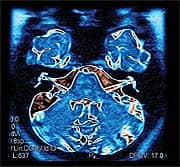

How Weight Harms HearingHow is obesity or excess weight related to hearing? Although that subject is only beginning to be studied, Swedish researchers did find a connection recently. They followed nearly three hundred Swedish women over a twenty-four-year period. Using various data, including physical exams and brain scans, they found the first evidence that those with a high body mass index (BMI) throughout adult life had lost brain tissue when compared to women with lower BMIs. Loss of brain tissue occurred in the temporal lobe portion of the brain, where the auditory system is located, along with language, speech, memory, and comprehension.13

Why would weight affect the brain? There are three possible answers to that question. One, excess weight could increase the number of damaging free radicals in the body. Two, fat may produce harmful substances, such as growth factors and hormones, which can erode brain tissue. And three, excess fat might be responsible for hardening of the arteries (atherosclerosis) and result in limited oxygen flow to the brain. Another connection between obesity and hearing loss is suggested by recent findings from Great Britain linking excess weight with accelerated aging. In a study involving more than eleven hundred women, scientists found that obesity had a greater effect on markers of aging than smoking. Among women who were obese, the markers showed signs of aging that were the equivalent of nearly nine years beyond those who were lean. Not surprisingly, being overweight or obese increases freeradical levels in the body, which the experts believe to be the reason more signs of aging were seen in those of excess weight.14